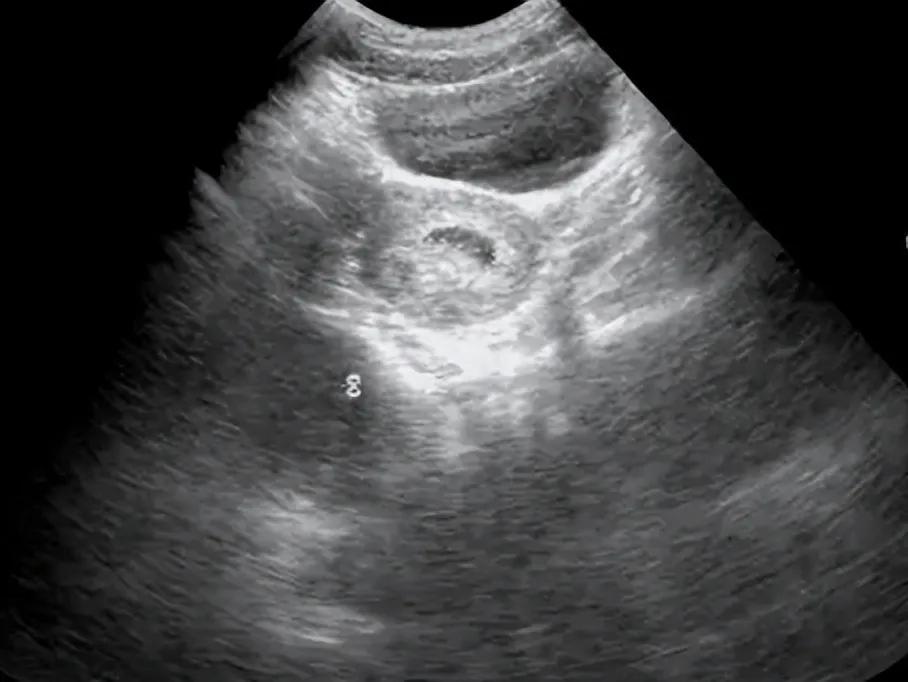

在促排卵阶段,B超检查成为监测卵泡发育的“得力助手”。医生通过定期检查,可以实时掌握卵泡的大小、形态和生长速度,从而精确调整用药剂量,确保卵泡能够健康发育。当多数卵泡大小达到18-25mm左右时,医生会安排取卵,为后续的胚胎培养做好准备。

在胚胎移植前,B超检查用于评估子宫内膜的状况。理想的子宫内膜厚度(8-12mm)、良好的血流和细胞分裂情况,都是提高胚胎着床率的关键因素。如果检查发现内膜偏厚或偏薄、回声不均等问题,可能需要调整移植计划或进行治疗。在移植当天,医生还会在B超引导下将胚胎移植管送入宫腔,选择最适宜的胚胎放置点,进一步提高成功率。

胚胎移植后10-14天,通过抽血检测HCG水平可以初步判断是否怀孕。如果确认怀孕,大约在移植后4-5周,B超检查将再次发挥作用,确认宫内妊娠并监测胚胎的早期发育情况。这一步骤对于排除宫外孕等风险至关重要。